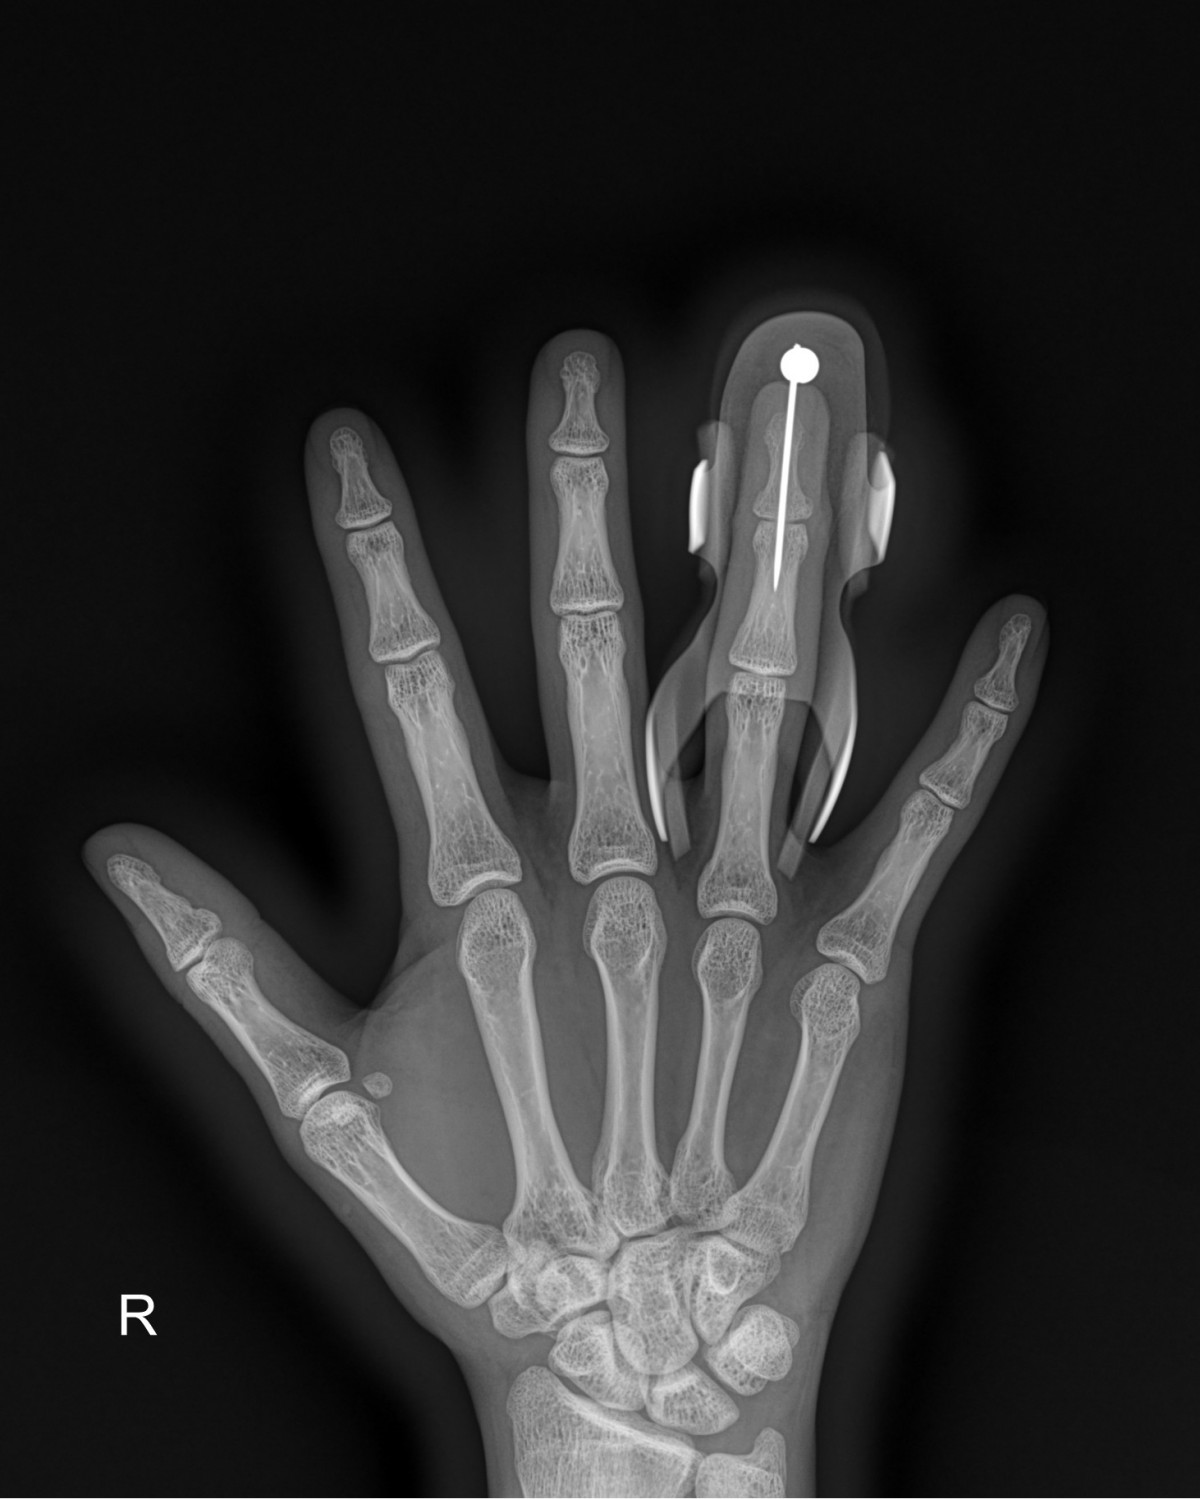

정지영원장님 손가락 골절 수술 안기O 환자

dae765e4d9ac96aee867c9d6292d8784_1758008508_6733.jpg